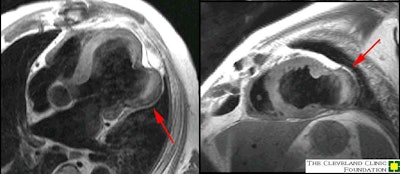

Left ventricular pseudoaneurysm: Pseudoaneurysm of the mid free wall of the left ventricle. Note that this is an atypical location - the usual location is inferobasilar/posterior wall. Case from Dr. Scott Flamm. |